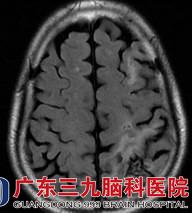

入院后医生查体,刁先生的语言不够流利,张口有限制,颅脑MRI提示:1.左侧额顶叶多发软化灶形成伴胶质增生、局限性脑萎缩,待排部分皮层层状坏死可能;2.双侧基底节-放射冠区、双侧丘脑、左侧半卵圆中心多发陈旧性腔梗灶;3D-ASL提示:左侧额顶枕叶呈低灌注;颈动脉彩超提示:双侧颈动脉粥样硬化(软斑);斑块造成左侧颈内动脉起始段重度狭窄。DSA提示:左侧颈内动脉起始部重度狭窄,狭窄率约80%。

图 1 术前MRI提示:左侧额顶叶多发软化灶形成伴胶质增生;